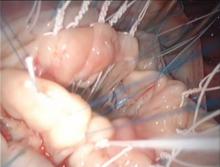

Figure 7. The folding of both leaflets.

- The principle of basal-marginal chordae equivalence is also considered. The height of a marginal chord is equal to that of the corresponding basal chord (Figure 1 [10], 2 [11], 3 [12]). A pliable leaflet can be folded, and its free margin can be temporarily approximated edge-to-edge to the adjacent annulus that is used as the reference point while the neochord is tied. In this position, the length of the neochord will correspond to the height of the basal chord. After unfolding of the leaflet, the neochord will recover its marginal position and the adjusted basal height will turn into the equivalent marginal height. Its final length will exactly match the plane of the annulus at the coaptation point (Figure 7 [16]).